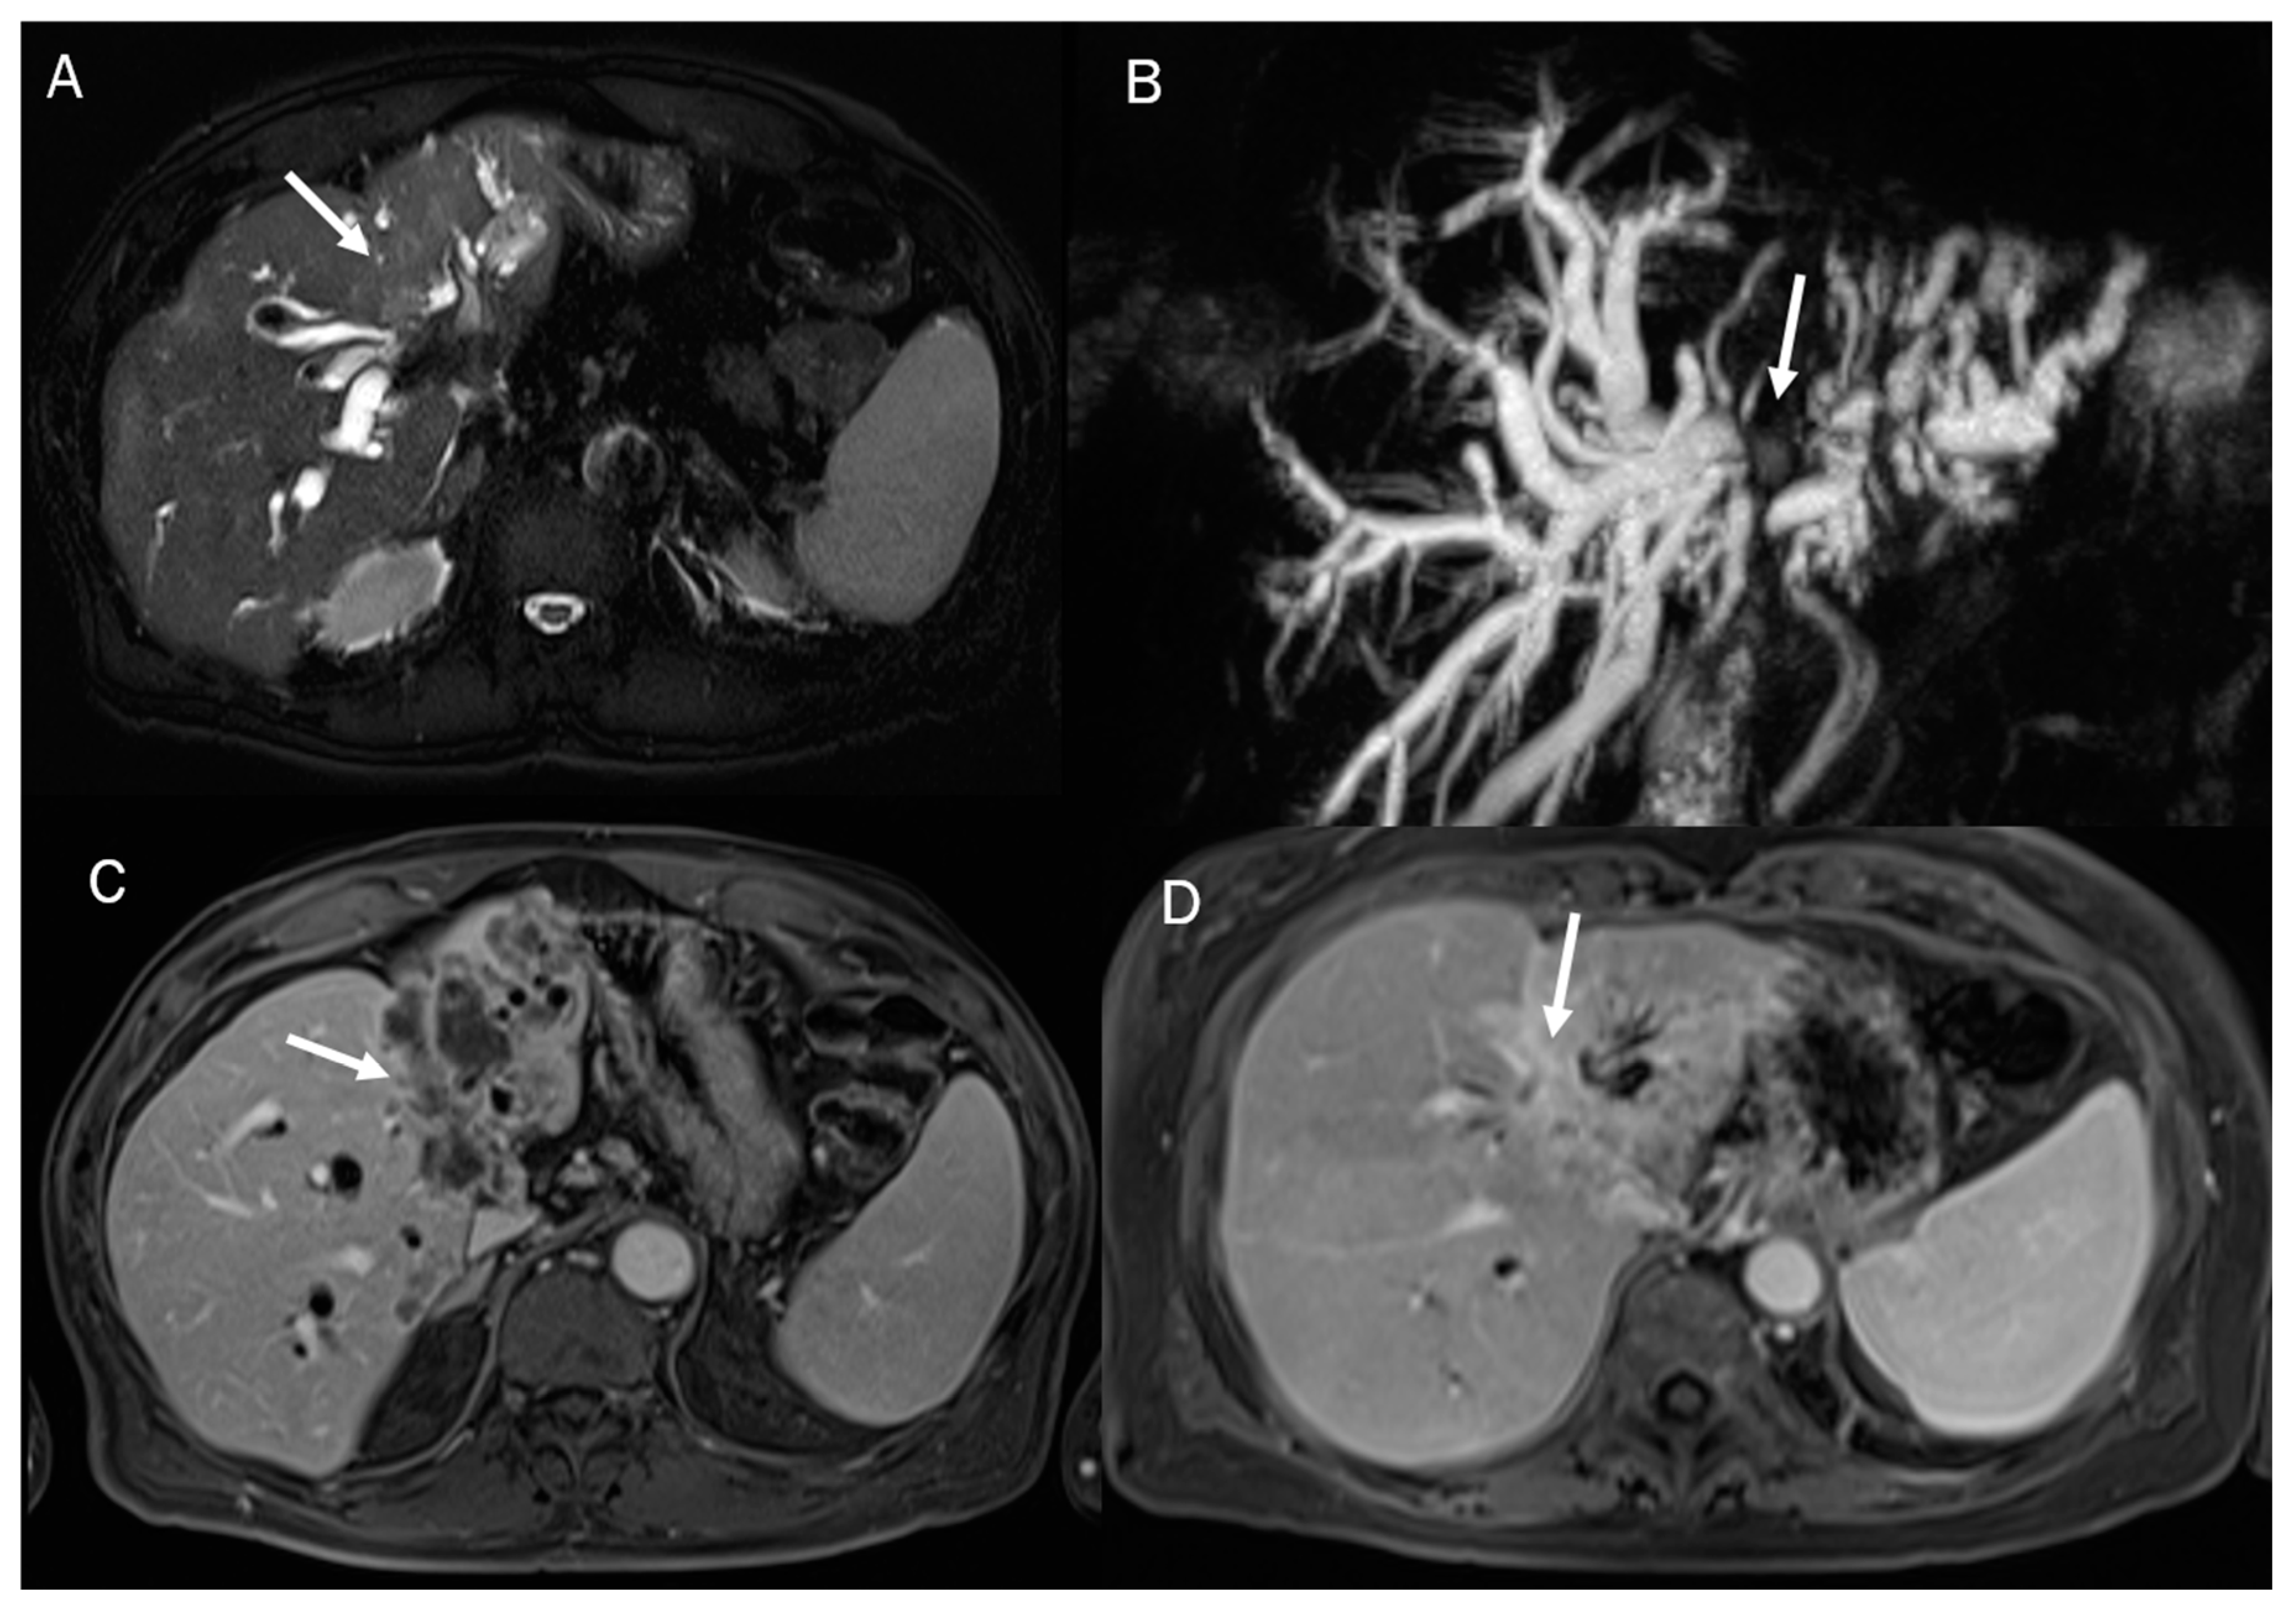

- Jhaveri, K.S.; Hosseini-Nik, H. MRI of cholangiocarcinoma. J. Magn. Reson. Imaging 2015, 42, 1165–1179. [Google Scholar] [CrossRef] [PubMed]

- Zhou, Y.; Zhou, G.; Zhang, J.; Xu, C.; Wang, X.; Xu, P. Radiomics signature on dynamic contrast-enhanced MR images: A potential imaging biomarker for prediction of microvascular invasion in mass-forming intrahepatic cholangiocarcinoma. Eur. Radiol. 2021, 31, 6846–6855. [Google Scholar] [CrossRef]

- Xu, L.; Wan, Y.; Luo, C.; Yang, J.; Yang, P.; Chen, F.; Wang, J.; Niu, T. Integrating intratumoral and peritumoral features to predict tumor recurrence in intrahepatic cholangiocarcinoma. Phys. Med. Biol. 2021, 66, 125001. [Google Scholar] [CrossRef]

- Zhao, L.; Ma, X.; Liang, M.; Li, D.; Ma, P.; Wang, S.; Wu, Z.; Zhao, X. Prediction for early recurrence of intrahepatic mass-forming cholangiocarcinoma: Quantitative magnetic resonance imaging combined with prognostic immunohistochemical markers. Cancer Imaging 2019, 19, 49. [Google Scholar] [CrossRef]

- Xu, L.; Yang, P.; Liang, W.; Liu, W.; Wang, W.; Luo, C.; Wang, J.; Peng, Z.; Xing, L.; Huang, M.; et al. A radiomics approach based on support vector machine using MR images for preoperative lymph node status evaluation in intrahepatic cholangiocarcinoma. Theranostics 2019, 9, 5374–5385. [Google Scholar] [CrossRef]